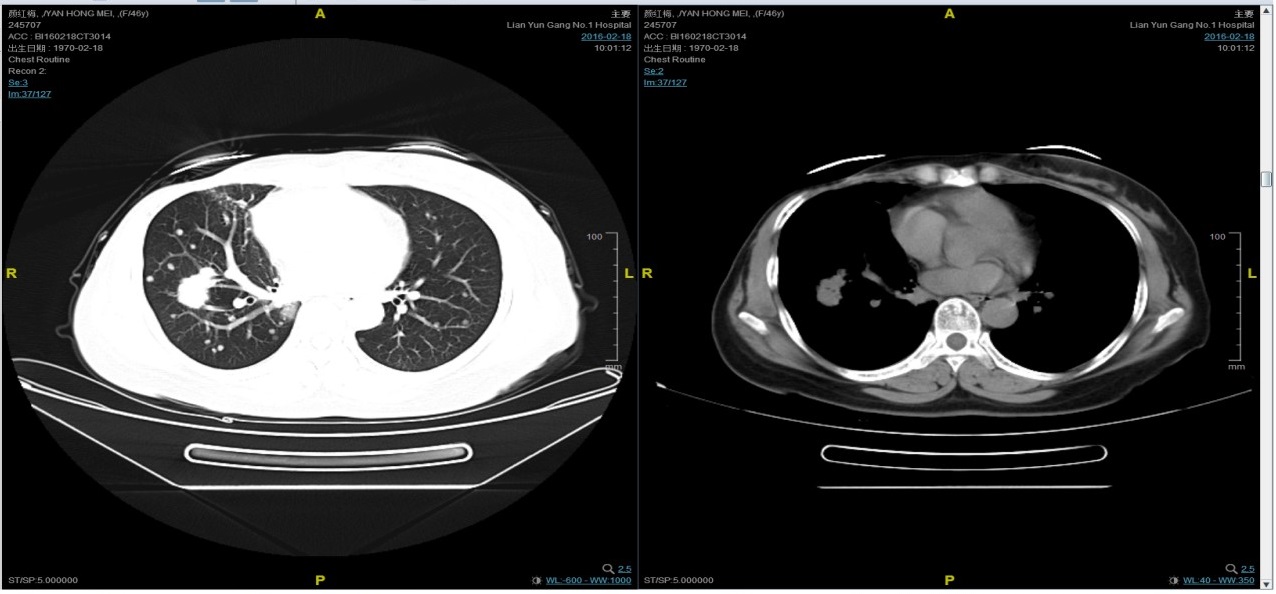

随访至2016-2-18,肺部病灶进展,肺内转移病灶增多。PFS2=10个月。

三线解救治疗及评价

从2016-2-19开始给予紫杉醇+曲妥珠单抗治疗,紫杉醇240mg,3周重复,曲妥珠单抗330mg三周重复。患者末次应用曲妥珠单抗和紫杉醇时间为2016-6-24,紫杉醇共应用4周期。

患者颜X X,女,发病年龄43岁。2010.12.01因体检发现右乳质硬、无痛性肿块住院治疗。入院查体肿块约2.5cm × 1.5cm。考虑诊断为右侧乳腺癌。2010.12.06在我院全麻下“右乳癌改良根治术”。术后病理:(右)乳腺浸润性导管癌,组织学分级Ⅲ级;乳头、皮肤未见癌累及,同侧腋窝淋巴结转移(19/19)。免疫组化:ER(-),PR(-),C- erbB-2(3+)。术后诊断右乳浸润性导管癌并右侧腋窝淋巴结转移(pT2N3M0,IIIC期,HER2阳性型)。术后于2011-01-06起在连云港市第一人民医院给予AC方案化疗4周期,2011-03-20给予右胸壁+右锁骨上下淋巴引流区放疗Dt50Gy/25f,2011-05-26予TH方案化疗4周期(曲妥珠单抗d1首次480mg,以后360mg)共4周期。后续予以曲妥珠单抗360mg(每21天为一周期)维持治疗1年,末次使用曲妥珠单抗的时间在2012年5月,后定期随访,病情稳定。2013-11-23全面复查发现肺转移。 DFS=35个月。2013-11-26起给予曲妥珠单抗(440mg d1)/脂质体紫杉醇(240mg d2)/CBP(500mg d2)方案化疗一个周期,出现Ⅱ度骨髓抑制,因患者主诉乏力明显,后修改方案曲妥珠单抗(330mg 每 3周重复)/脂质体紫杉醇(120mg d1+d8+d15,每4周重复)化疗,化疗过程顺利,患者无明显骨髓抑制,无乏力主诉,于2014-02-11全面复查,疗效评价为PR。继续曲妥珠单抗+脂质体紫杉醇(共六周期)治疗,疗效评价CR。后续予以曲妥珠单抗维持治疗,随访病情稳定。2015年4月,患者肺部病灶复发。给予曲妥珠单抗+希罗达治疗(希罗达1500mg,一天两次口服)。PFS1=17个月。2016-2-18,肺部病灶进展,肺内转移病灶增多。PFS2=10个月。从2016-2-19开始给予紫杉醇+曲妥珠单抗治疗,紫杉醇240mg,3周重复,曲妥珠单抗330mg三周重复。患者末次应用曲妥珠单抗和紫杉醇时间为2016-6-24,紫杉醇共应用4周期。CT评价SD。继续曲妥珠单抗维持治疗,且自服中药。2017-02-27患者因气喘胸闷再次就诊。患者肺部病灶进展,同时出现肝脏转移。再次给予曲妥珠单抗+长春瑞滨化疗一周期,效果不佳,患者放弃治疗。PFS3=12个月。